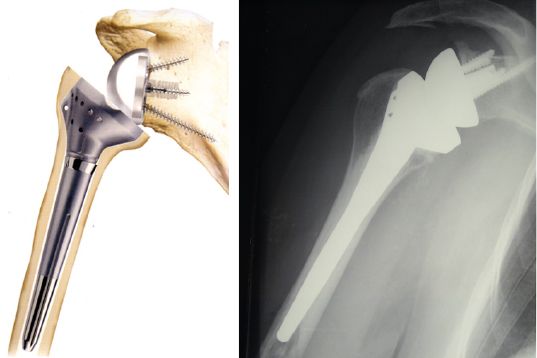

Biomécanique Prothèse inversée d’épaule et latéralisation , Luc Favard CHU Trousseau, 37044 Tours, France N°308 - Novembre 2021 ● 9 min de lecture

Biomécanique Quoi de neuf en biomécanique des prothèses d’épaule inversées ? , Pierre-Henri Flurin Clinique du Sport - Bordeaux-Mérignac, Mérignac, France 🖂 phflurin@gmail.com , C. Roche Gainesville, FL - , L. Crosby Augusta, GA - , T. Wright Palm Beach, FL - , J. Zuckerman New-York, NY N°239 - Décembre 2014 ● 16 min de lecture